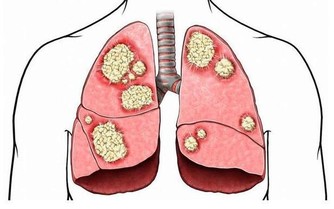

全年逾500萬人感冒

林口長庚醫院藥劑部臨床藥學科藥劑師遊佳玲指出,根據衛福部統計資料顯示,2014年國人因上呼吸道感染至門診就醫者高達585萬人。其實感冒大多由病毒引起,通常會出現咳嗽、流鼻水、打噴嚏、喉嚨痛、頭痛及全身痠痛等症狀,而市售的綜合感冒藥、感冒糖漿含有多種成分,最常見的成分是解熱鎮痛藥,對緩解感冒的咳嗽、流鼻水症狀沒有幫助。